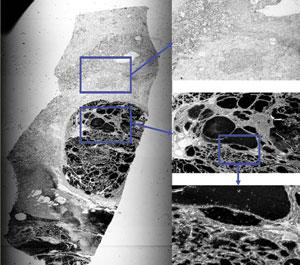

Engineers at Biomedical Photometrics (Waterloo, Ont., Canada) have developed an alternative technique that relies on raster-scanning of laser light through a telecentric lens, coupled with a precisely moving specimen-bearing stage, to capture confocal images as large as 22 × 70 mm in a matter of minutes (see figure). The system-called the Tissuescope-has just been commercially introduced.The image captured by the Tissuescope has dimensions determined in one axis by the field size of the telecentric lens, and in the other by the length of a microscope slide. One microscope version has a telecentric lens with a numerical aperture of 0.35, a best-pixel resolution of 1 µm, a working distance of 6 mm, and a 20- to 22-mm field, depending on the type of contrast mechanism used. For brightfield, the image size with this lens is 20 × 70 mm, while for fluorescence it is 22 × 70 mm. Another version of the instrument contains a telecentric lens with a numerical aperture of 0.5, a best-pixel resolution of 0.25 µm, a working distance of 3 mm, and a field size of 10 mm. The microscopes can also be operated at reduced resolution, with pixel sizes ranging from 2 to 100 µm.

Transmission images (most similar to conventional brightfield microscope images) can be captured in full color. Fluorescent images (in which a biological specimen is prepared with a fluorescent dye) are obtained in a reflection mode; simultaneous three-channel fluorophore detection is possible. Transmitted-light and fluorescence images can be acquired at the same time and the images merged with software, highlighting the exact location of labeled cells within the tissue specimen. Because some types of tissue naturally fluoresce without the need for dyes, autofluorescent imaging is sometimes possible. Nonfluorescent reflected-light imaging can be carried out with the tissue in an unstained state or labeled with a reflective probe substance. Finally, a differential-phase-contrast approach can be used to enhance edges.

The ability to image large-area specimens is important particularly in examining whole-organ tissue slices, notes Smith. “A common desire in drug development and cancer-therapeutics research is to see the localization of a drug throughout a sample or the effect of the drug throughout the organ,” he says. “Also, in the area of stem-cell research, there is a desire to see where the stem cells go and how they congregate through the specimen.”